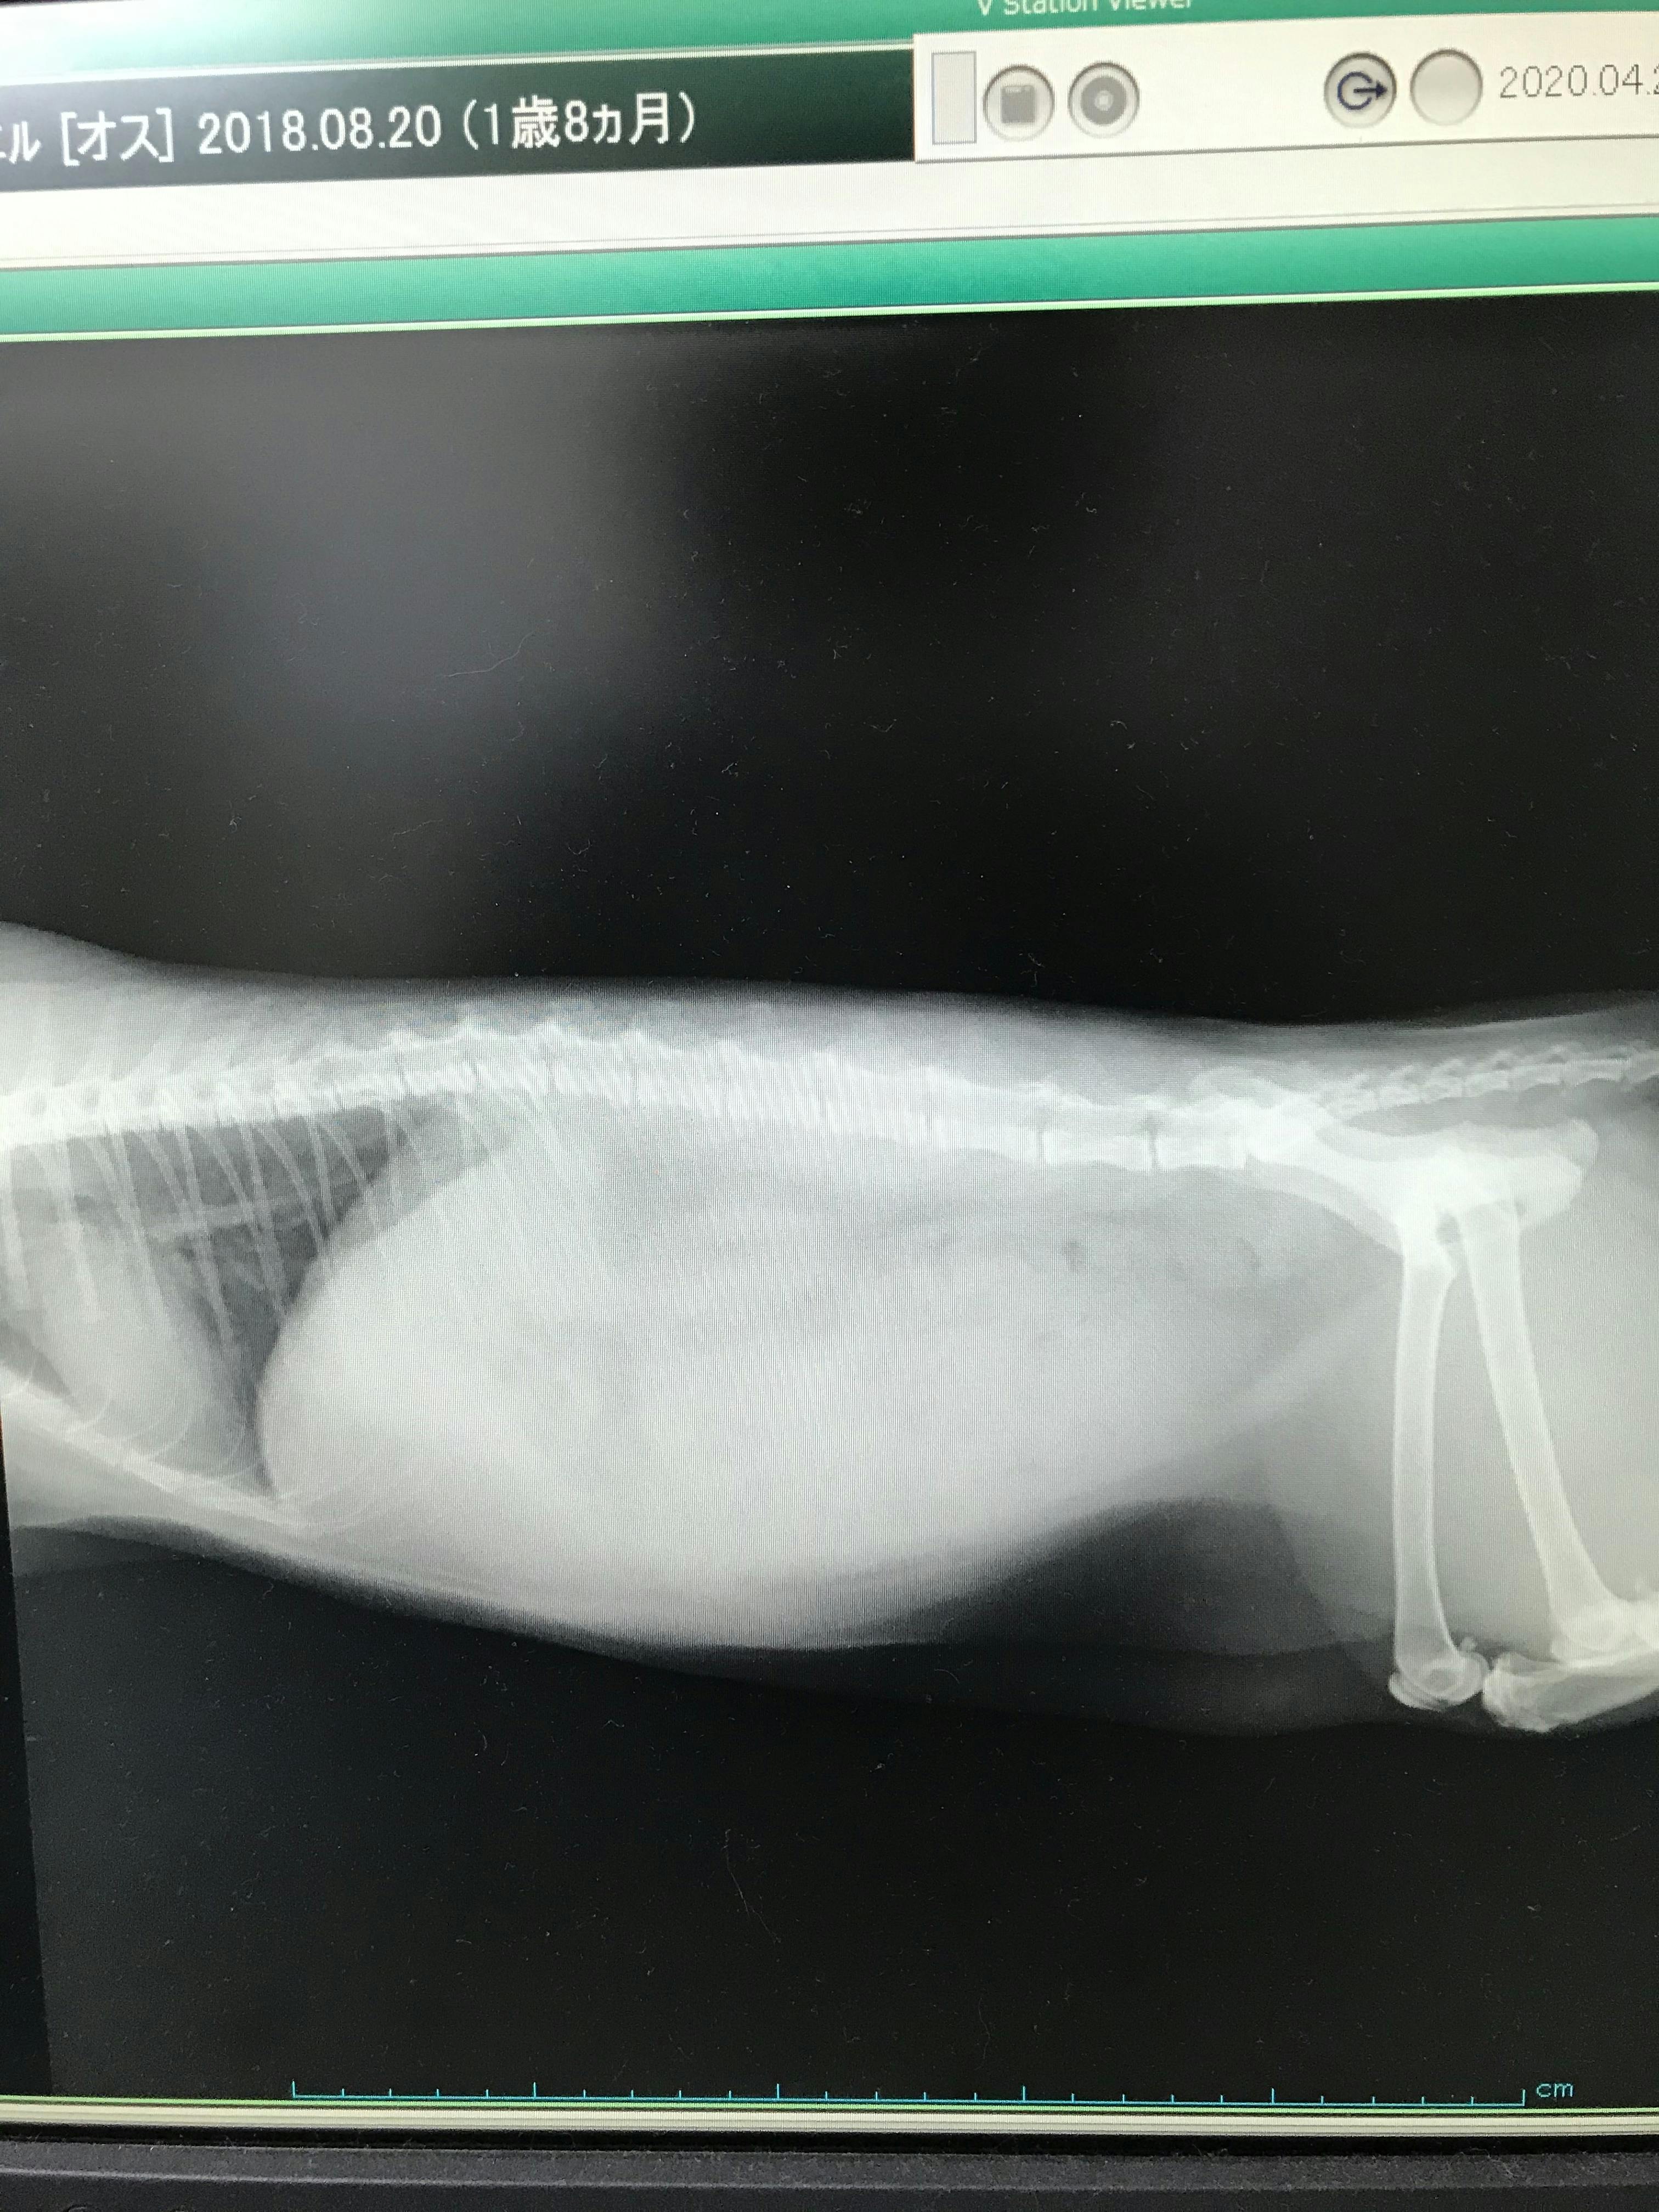

ドライ ウェット 診断. プ,ドライタイプを呈する1).確定診断は生検で免疫 染色を行い,fipv 抗原を検出することがゴールドス タンダードであるが,近年では定量 rt-pcr 法によ りfecov とfipv との区別が可能となり,診断でき るようになっている1 )4 .近年,胸水を伴うウェット. ウェットタイプはドライタイプよりも 生産コストがかかってしまう ので、どうしても価格が上がってしまうんです。 「価格はなるべく抑えたい…」というときは、ファインペッツのようなコスパが良くてドライタイプのキャットフードを選ぶのがいい. ベースになるのはすべて毛髪診断です。 ウェット&ドライの毛髪方法でみられれば、 失敗のないヘアデザインを提案できるようになります。 流山市美容室ヘアサロンウェーブは、 ブログで美容情報を更新しています。.

ドライタイプの症状か Campfire キャンプファイヤー

猫伝染性腹膜炎 埼玉県久喜市 シロー動物病院のブログ